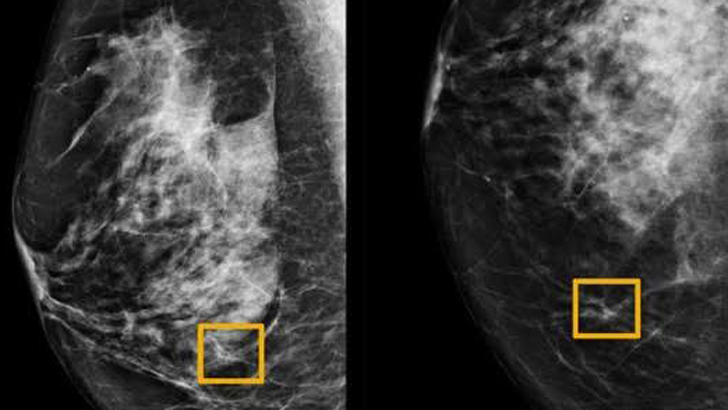

স্তন ক্যান্সার শনাক্তে গুগল এআইয়ের বিস্ময়কর সফলতা

বাংলানিউজসিএ ডেস্ক :: স্তন ক্যান্সার শনাক্ত করতে গুগলের কৃত্রিম...